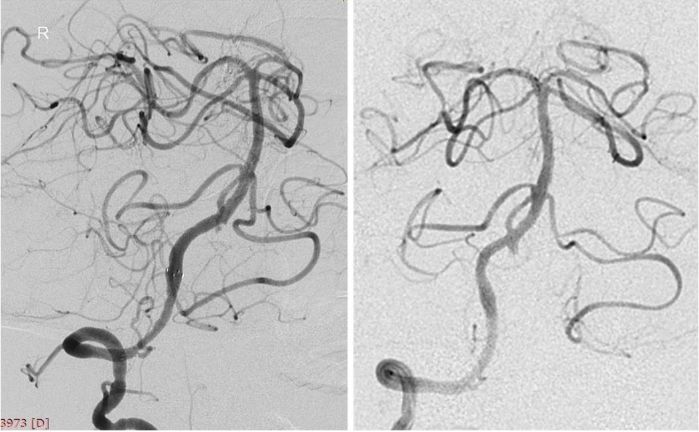

外院DSA:右椎动脉V4段次全闭塞,基底动脉有顺向显影,前向血流减慢;左椎动脉V3段闭塞,见基底动脉经脊髓前动脉代偿显影(图3,4)。

图3

图4